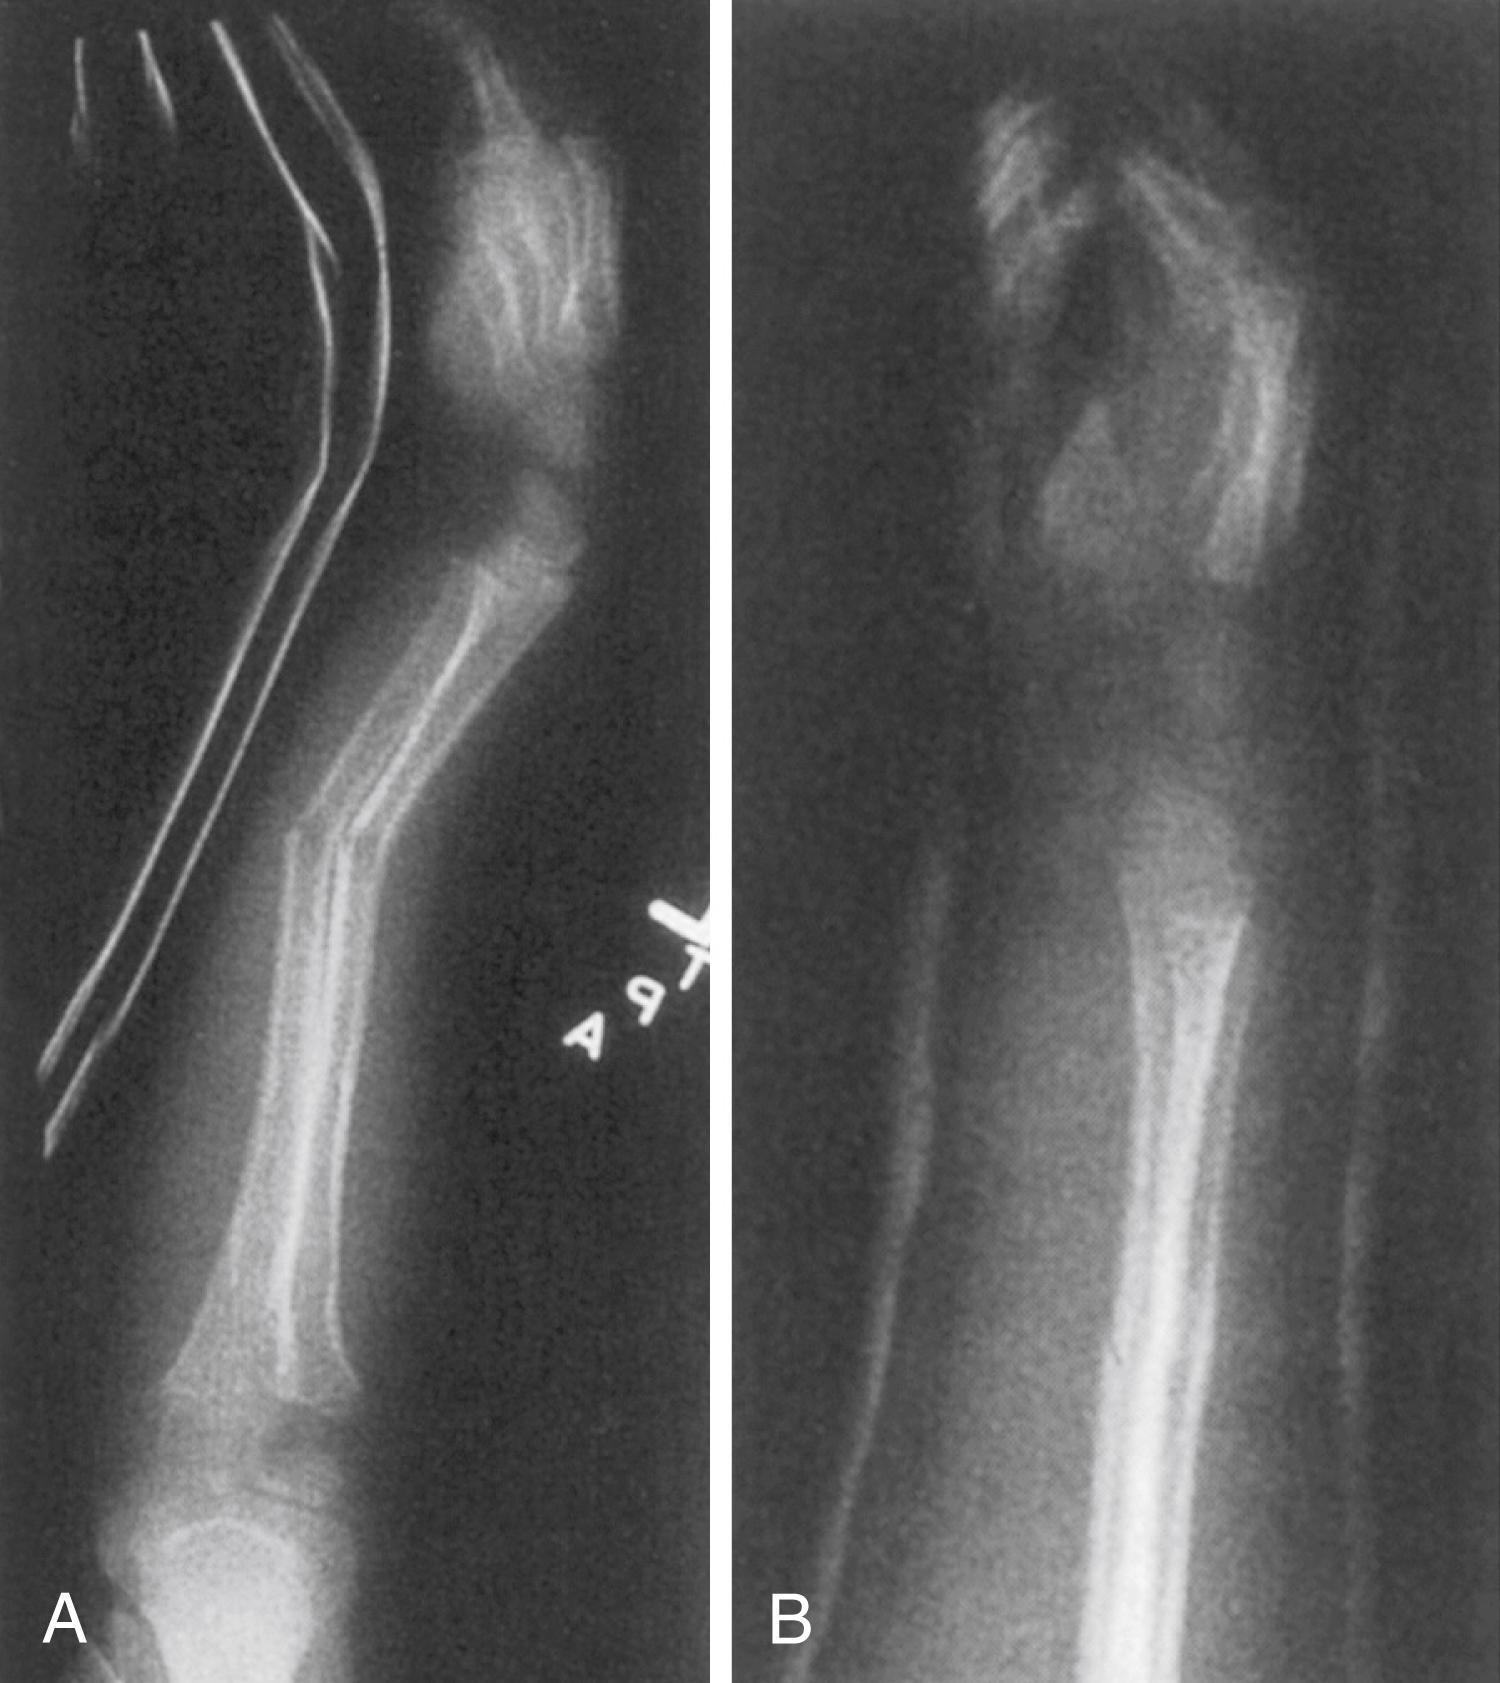

Fig. 27.13, Salter-Harris type II fracture of the right distal femur complicated by pin tract sepsis and complete physeal arrest. (A) Anteroposterior radiographs of the right and left knees. The uninvolved left knee has a healthy-appearing distal femoral physis. On the right side there is no radiolucency corresponding to the physis. (B) Tomograph revealing a small amount of physis on the far medial aspect of the right distal femur. Most of the physis has been replaced by radiodense scar. Radiographic evidence of the cross pins is present on the plain radiograph and tomograph.